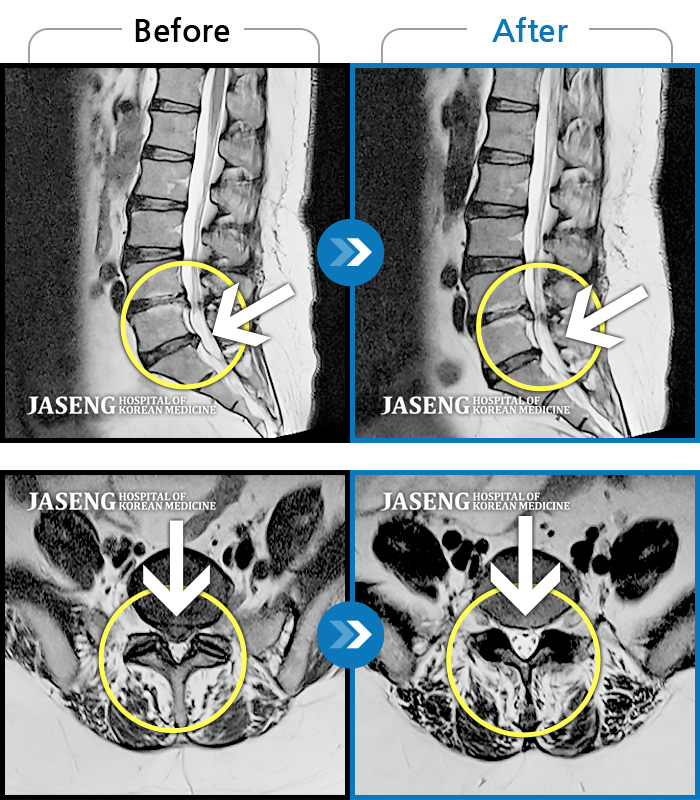

MRI 치료사례

허리 골반 통증, 왼쪽 허벅지에서 종아리 발까지 당김 증세 및 통증